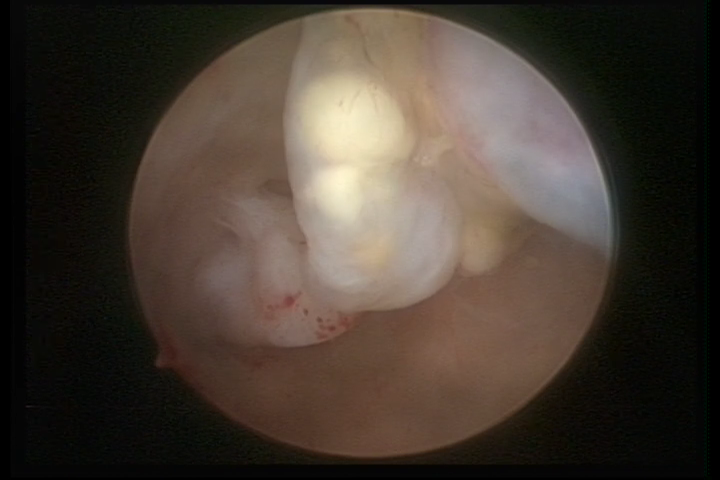

Este pode apresentar uma gama variável de aspectos macroscópicos, com aspecto pseudopolipoide; lembrando tecido cerebroide ou com reação deciduoide; a vascularização superficial é mais evidente e com vasos em formatos de saca-rolha ou espirais visualizando também a vascularização com atipias, com aumento do calibre dos vasos superficiais, pode ser encontrado também tecido em necrose, poderá haver pequenos dendritos (papilomatoso).